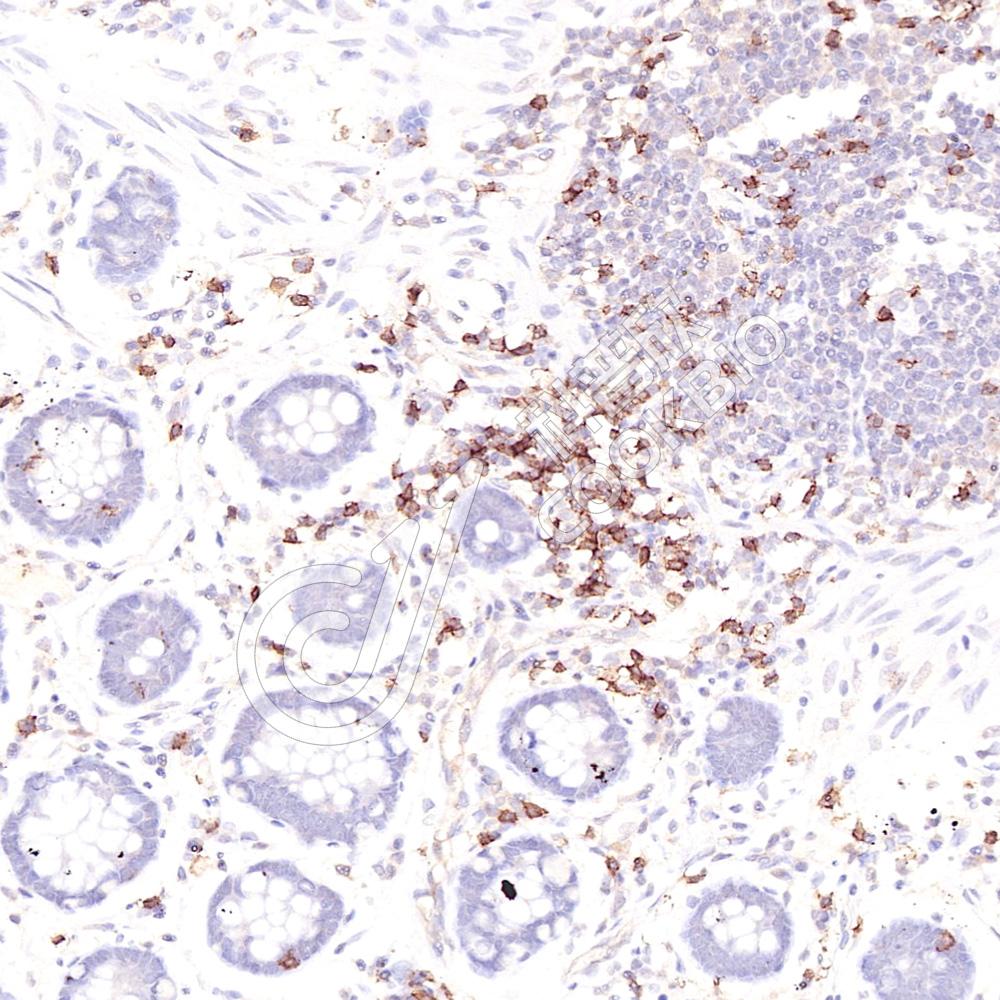

IHC检测Fc epsilon RI/FCER1A蛋白(货号 K1339498).

样品: 大鼠脾, 4%多聚甲醛 (货号KSG1101) 固定12-24小时.

抗原修复: 柠檬酸抗原修复液(干粉, pH 6.0) (KSG1201), 98℃, 20分钟.

—抗: 1: 1400稀释, 4℃ 孵育过夜.

二抗: S-vision免疫组化多聚二抗(山羊抗兔),即用型 (货号KB3906), 室温孵育20分钟.